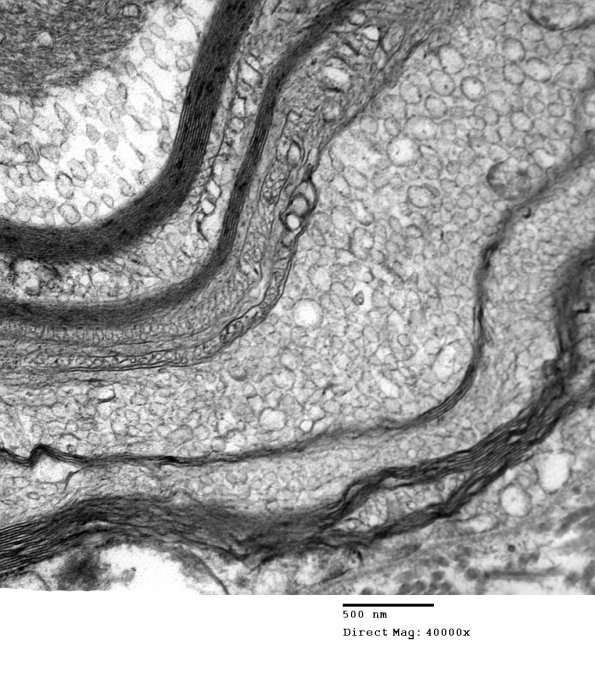

Higher magnification of image #19B1. (electron micrograph)